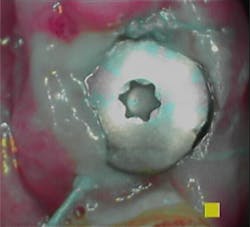

Assess the implant to diagnose its condition or health, including any hard- and soft-tissue deficiencies. Follow the Wingrove five-step implant assessment, which starts by assessing the tissue surrounding the implant, known as the perimucosal seal, for any inflammation that may be present. (3)

Note in the patient’s record whether any inflammation is visually present by using an intraoral camera if possible. Use the Gingival Index rating to assess the inflammation level on a scale of 1–3: mild, moderate, or severe (figures 1a–1c).